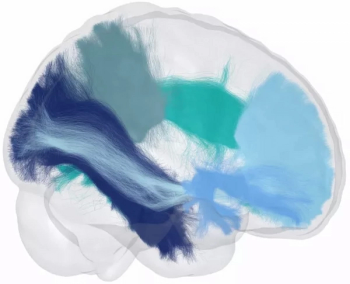

In their review of functional MRI data from over 5,200 study participants, researchers noted that higher amygdala reactivity and lower prefrontal cortical reactivity were associated with adversity exposure, findings that may contribute to exaggerated threat detection and reduced emotional control.